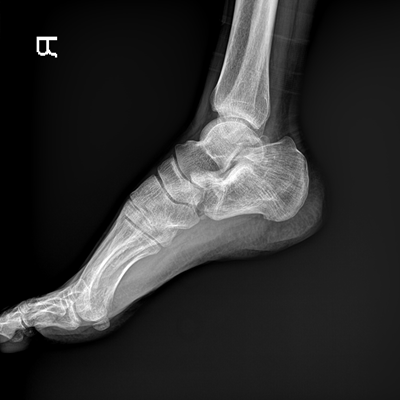

●大尺寸非晶硅平板探測器。

●探測器可以大范圍轉動,大尺寸有效探測面積,可滿足人體多部位攝影需求。